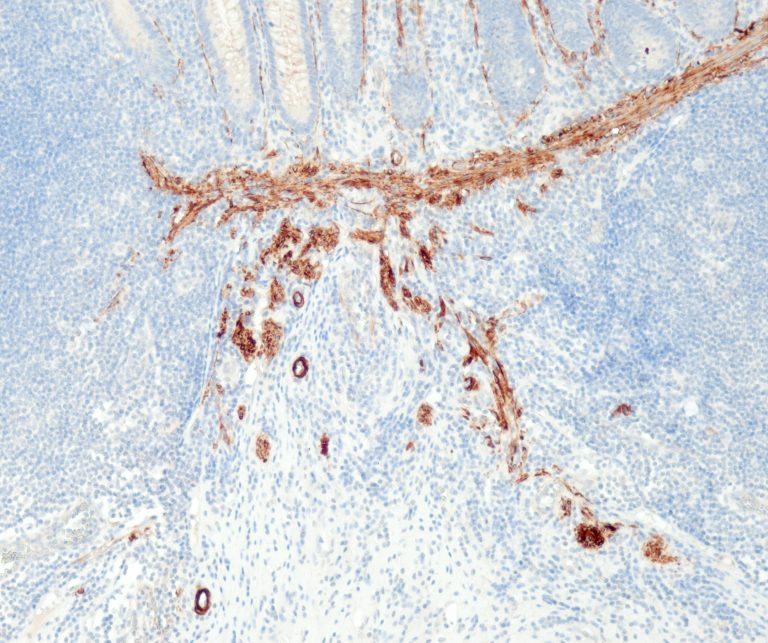

Vascular Pathology

Gastrointestinal (GI) Pathology